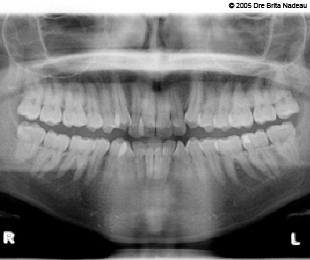

- Photos & radiographies